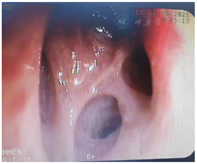

2020年7月15日气管镜:左支气管各管腔通畅,未见新生物及狭窄;右上叶支气管尖段开口见新生物生长,堵塞管腔(图1),活检易出血;右中、下叶管腔通畅,未见新生物及狭窄。刷检涂片查见癌细胞,活检病理提示鳞状上皮呈高级别上皮内瘤变(图2),局部考虑癌变。